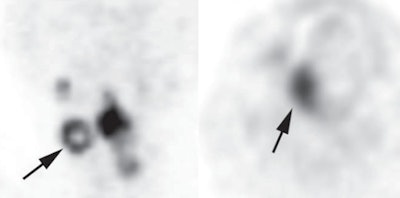

Left PET image shows typical ring-shaped uptake (arrow) in metastatic lymph node of a 54-year-old woman with hypopharyngeal squamous cell carcinoma. Sphere-shaped uptake shown at right is from a primary lesion in a 55-year-old man with SCC of the oral cavity. Images courtesy of AJR."Our findings suggest that the uptake pattern on FDG-PET/CT can provide better prognostic information than conventional quantitative patterns," the authors wrote. This could be because uptake patterns better reflect intratumoral necrosis or heterogeneous morphology, they added.

As good as these quantitative factors were, the shape of FDG uptake was better. Patients with sphere-shaped patterns of FDG uptake were almost 19 times more likely to survive than those with ring-shaped patterns (hazard ratio = 18.92).

Of the 108 patients, 14 had ring-shaped patterns and 94 had sphere-shaped patterns. Approximately 90% of those with sphere-shaped patterns survived for more than six years. In comparison, 10% of subjects with ring-shaped patterns survived for more than 36 months.